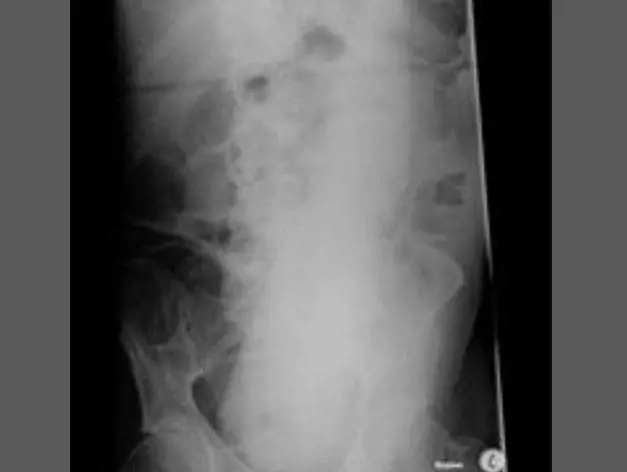

Oggetti bizzarri che hanno trovato la loro strada all'interno del corpo umano, e documentati grazie alle pazze radiografie raccolte dal dottor Frank Gaillard. Quest’ultimo ha fondato Radiopaedia.org, un sito collaborativo che raccoglie casi radiologici e articoli medici a tema.